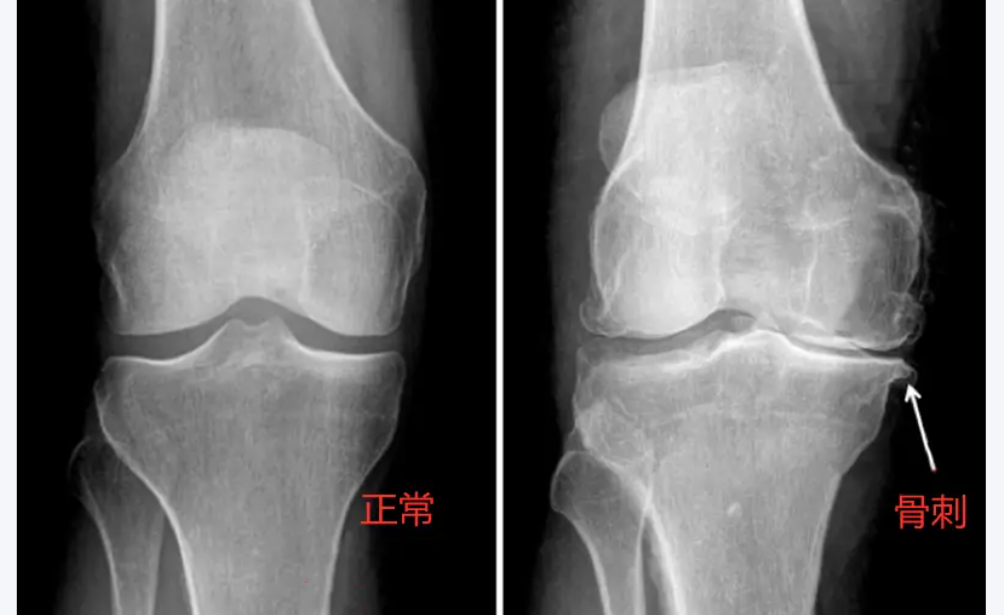

2、骨质增生(骨刺):软骨磨损后,骨头边缘为增加稳定性而代偿性增生(起初是良性增生),形成骨赘(骨刺),进一步刺激周围组织引发疼痛。

忽视早期的代价是沉重的:当疾病进展到中晚期(软骨大面积磨损或剥脱、骨刺大量增生、关节严重变形),疼痛持续剧烈、关节活动度显著受限(无法伸直或弯曲)、跛行甚至影响睡眠。此时保守治疗往往杯水车薪,关节镜清理术效果有限且不持久,最终多数患者不得不面临创伤大、费用高、恢复期长的全膝关节置换术。